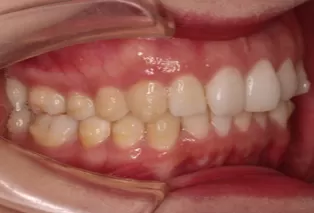

Photos intra-orales